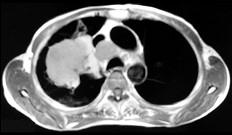

问题 男,68岁,右侧胸痛伴右上臂麻木一周,胸部CT、MRI扫描如图,最可能的诊断为 ( )

选项 A、右上肺中央型肺癌并右上肺不张,纵隔淋巴转移 B、右上肺周围型肺癌并纵隔淋巴转移 C、右上肺肉瘤并纵隔淋巴转移 D、右上肺不张 E、右上肺硬化性血管瘤

答案 A